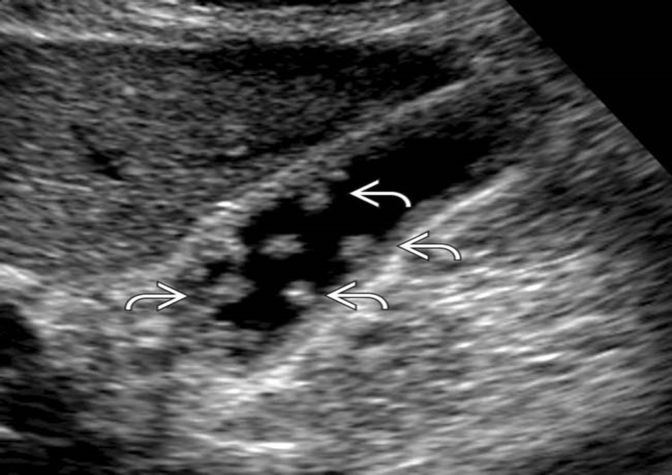

# 1 Pt. c/o RUQ pain, this image looked the same in both supine and LLD positions. Name the pathology

Cholesterolosis showing multiple cholesterol polyps